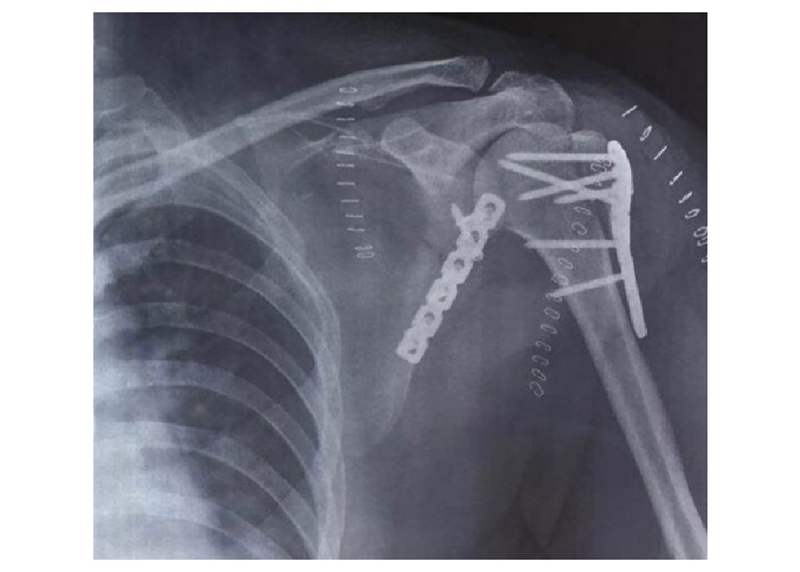

病例4为53岁男性患者,因高处坠落导致右肩胛骨骨折,合并右侧第3、5、7、8肋骨骨折(图20-21)。

术中采用钢板固定肩胛颈内下方骨折块,肩胛骨体部骨折固定采用缝线辅助固定技术,骨折端以Nice结固定。术后CT三维重建显示骨折复位满意,固定良好(图22)。

图22 术后CT三维重建示肩胛骨骨折复位满意,内固定位置良好 图A:肩胛骨后面观;图B:肩胛骨侧面观